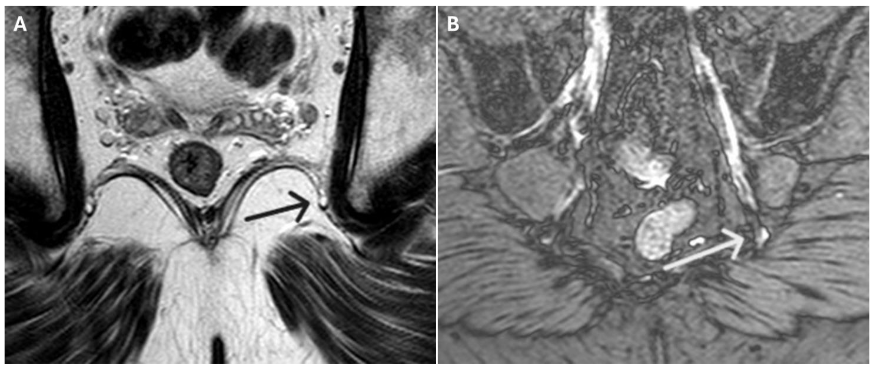

In cases of injury, the pudendal nerve appeared as a hyperintense linear structure on DP SPAIR double IR BB sequences. Coronal oblique views were optimal for visualizing the nerve’s exit and re-entry near the ischial spine, while axial oblique views best depicted its course through Alcock’s canal.

Additional diagnostic criteria included:

- Architectural distortion, deviation, caliber changes, and perineural fibrosis

- Loss of fascicular striation (longitudinal) or honeycomb pattern (axial)

- Irregular contours and abrupt caliber changes (entrapment neuropathy)

- Fat plane obliteration (perineural fibrosis)

- Onion-bulb appearance (chronic demyelinating polyneuropathy)

Among the etiologies, pudendal nerve entrapment at one of four anatomical sites is particularly significant: (a) at the piriformis muscle in the sciatic notch (Type 1); (b) at the ischial spine and sacrotuberous ligament (Type 2); (c) within Alcock’s canal along the medial surface of the obturator internus muscle (Type 3); and (d) distal to the urogenital diaphragm at the peripheral branches of the dorsal penile or clitoral nerves (Type 4). Other potential causes include post-herpetic, stretch-induced, or post-radiotherapy neuropathy; neoplastic compression or direct trauma; congenital or acquired peripheral polyneuropathies; and iatrogenic injury during surgery. Although a detailed discussion is beyond the scope of this article, it is helpful to be familiar with the fundamental pathological processes underlying peripheral neuropathy, including Wallerian degeneration, axonal disintegration, and the regenerative response to nerve injury. Readers interested in a comprehensive overview are referred to the seminal review by Gaudet et al., published in 2011.